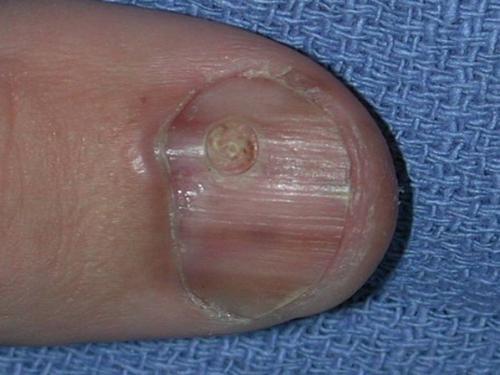

Признак I

Чаще всего подногтевая меланома проявляется в виде полоски коричневого или черного цвета. Полоска начинается от ногтевого валика и заканчивается на крае ногтя. Это состояние называется продольной меланонихией. Некоторые лекарственные препараты могут приводить к появлению таких полос – ретиноиды и Доцетаксел (Таксотер) . Этот признак может быть и при состояниях, не связанных с меланомой, например, при грибковом поражении ногтя, пигментном невусе ногтевого ложа.

Подногтевой пигментный невус у мальчика 13 лет

Подногтевая меланома I ст., 0,2 мм по Бреслоу